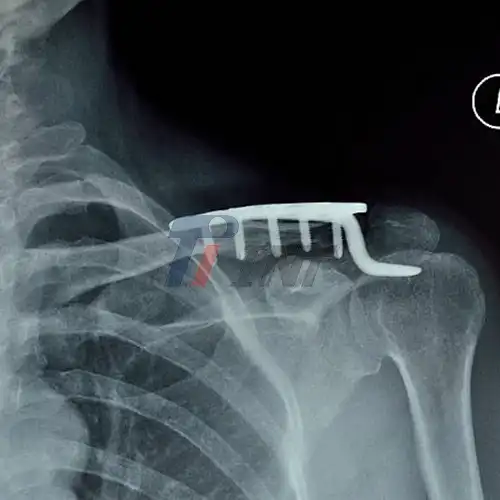

2026-01-15 08:50:16Sourcing Clavicle Titanium Plates from Baoji Industrial Park